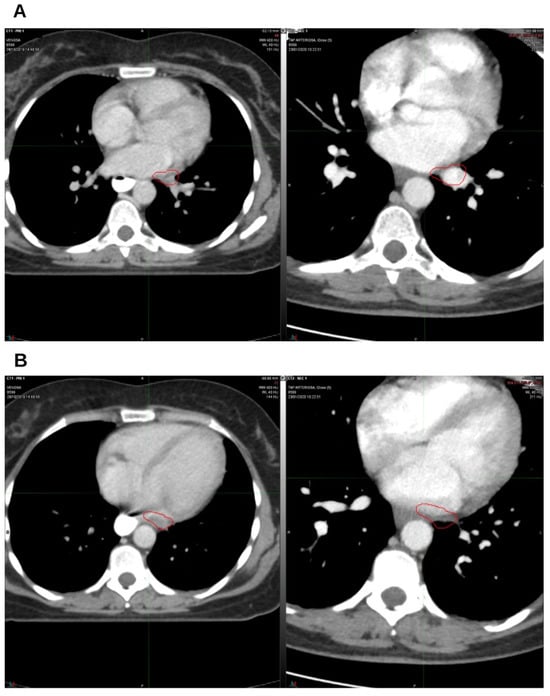

Integrative Use of Cannabidiol, Melatonin, and Oxygen–Ozone Therapy in Triple-Negative Breast Cancer with Lung and Mediastinal Metastases. A Case Report

Background and Clinical Significance: Breast cancer is the most frequent malignancy in women. Metastatic breast cancer is considered a treatable but incurable condition, with a median overall survival of only 2–3 years. Among its subtypes, triple-negative breast cancer (TNBC) accounts for a high proportion of breast cancer-related deaths. It is characterized by an aggressive clinical course, early recurrence, and a strong propensity for visceral and brain metastases. Case Presentation: We report the case of a Caucasian woman who developed systemic disease recurrence with lung and mediastinal lymph node metastases, occurring two years after her primary diagnosis and treatment for TNBC. The patient received three months of chemotherapy combined with an adjuvant integrative protocol consisting of melatonin, cannabidiol, and oxygen–ozone therapy. This combined approach led to the complete disappearance of the lung nodules. Subsequently, stereotactic radiotherapy was performed and, in association with the ongoing integrative treatment, resulted in a significant reduction in mediastinal adenopathy. Introduction of immunotherapy, supported continuously by the same adjuvant strategy, achieved a complete and durable remission. Strikingly, the patient remained disease-free five years after the diagnosis of lung and mediastinal metastases. Conclusions: This clinical case highlights the potential benefit of using melatonin, cannabidiol, and oxygen–ozone therapy as part of an integrative approach in patients with aggressive metastatic TNBC. While it is not possible to establish causality from a single case, the sustained remission observed suggests that such unconventional adjuvant strategies could play a supportive role in enhancing the efficacy of standard oncologic therapies. Full article

Figure 1